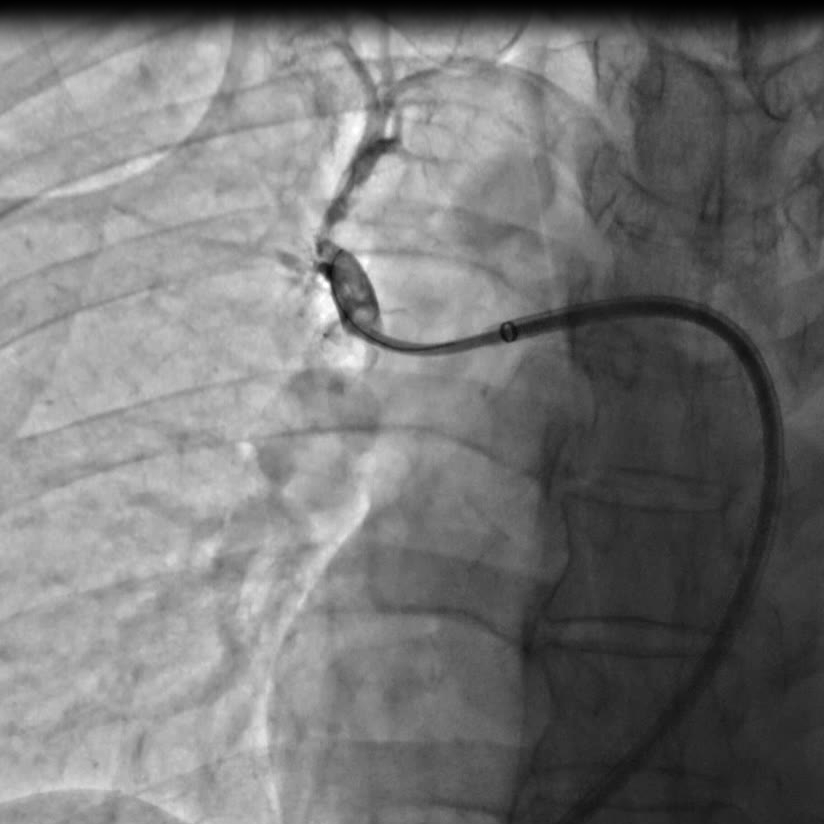

指引导管右肺A1段造影提示A1段近段次全闭塞

球囊扩张次全闭塞病变处

囊扩张术后狭窄改善的影像